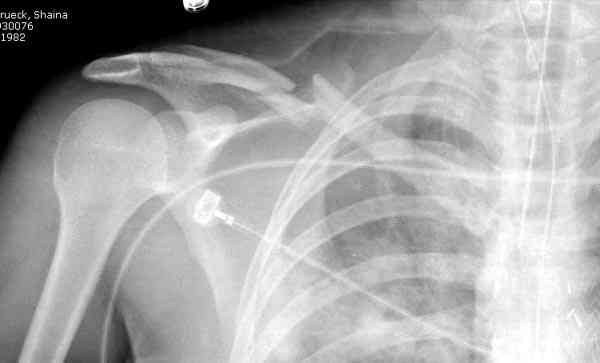

ГГШ> Результат стационарного лечения приведен на рентгенограмме (Xray_3).

Это картинка то есть через неделю после травмы, при выписке? Более чем приемлемо.

после изучения рентгенограмм могу сказать следующее:

1) после репозиции стало хуже

2) стояние фрагментов при выписке идентично таковому при пступлении - с выраженным смещением

Уважаемая Г.В. Полностью согласен с Вашим постом.Закрытая репозиция и кольца Дельбе отлично зарекомендовали себя за 35 лет практики. В обсуждаемом случае представленные Р-граммы сами говорят за себя, 1 снимок (до лечения) и 3 снимок (после лечения) абсолютно идентичны, 2 снимок сделан в несколько иной позиции.Как говорится "комментарии излишни". Согласитесь, что результат лечения мог бы быть и лучшим.